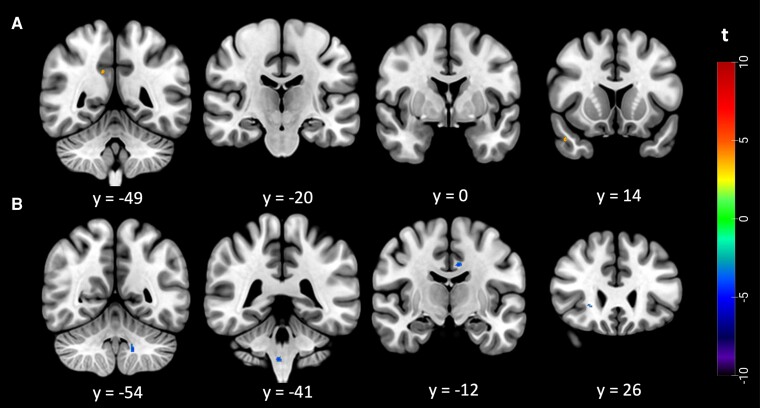

Amyotrophic lateral sclerosis, a progressive neurodegenerative disease, presents challenges in predicting individual disease trajectories due to its heterogeneous nature. This study explores the application of texture analysis on T1-weighted MRI in patients with amyotrophic lateral sclerosis, stratified by the D50 disease progression model. The D50 model, which offers a more nuanced representation of disease progression than traditional linear metrics, calculates the sigmoidal curve of functional decline and provides independent quantifications of disease aggressiveness and accumulation. In this research, a representative cohort of 116 patients with amyotrophic lateral sclerosis was studied using the D50 model and texture analysis on MRI images. Texture analysis, a technique used for quantifying voxel intensity patterns in MRI images, was employed to discern alterations in brain tissue associated with amyotrophic lateral sclerosis. This study examined alterations of the texture feature autocorrelation across sub-groups of patients based on disease accumulation, aggressiveness and the first site of onset, as well as in direct regressions with accumulation/aggressiveness. The findings revealed distinct patterns of the texture-derived autocorrelation in grey and white matter, increase in bilateral corticospinal tract, right hippocampus and left temporal pole as well as widespread decrease within motor and extra-motor brain regions, of patients stratified based on their disease accumulation. Autocorrelation alterations in grey and white matter, in clusters within the left cingulate gyrus white matter, brainstem, left cerebellar tonsil grey matter and right inferior fronto-occipital fasciculus, were also negatively associated with disease accumulation in regression analysis. Otherwise, disease aggressiveness correlated with only two small clusters, within the right superior temporal gyrus and right posterior division of the cingulate gyrus white matter. The findings suggest that texture analysis could serve as a potential biomarker for disease stage in amyotrophic lateral sclerosis, with potential for quick assessment based on using T1-weighted images.